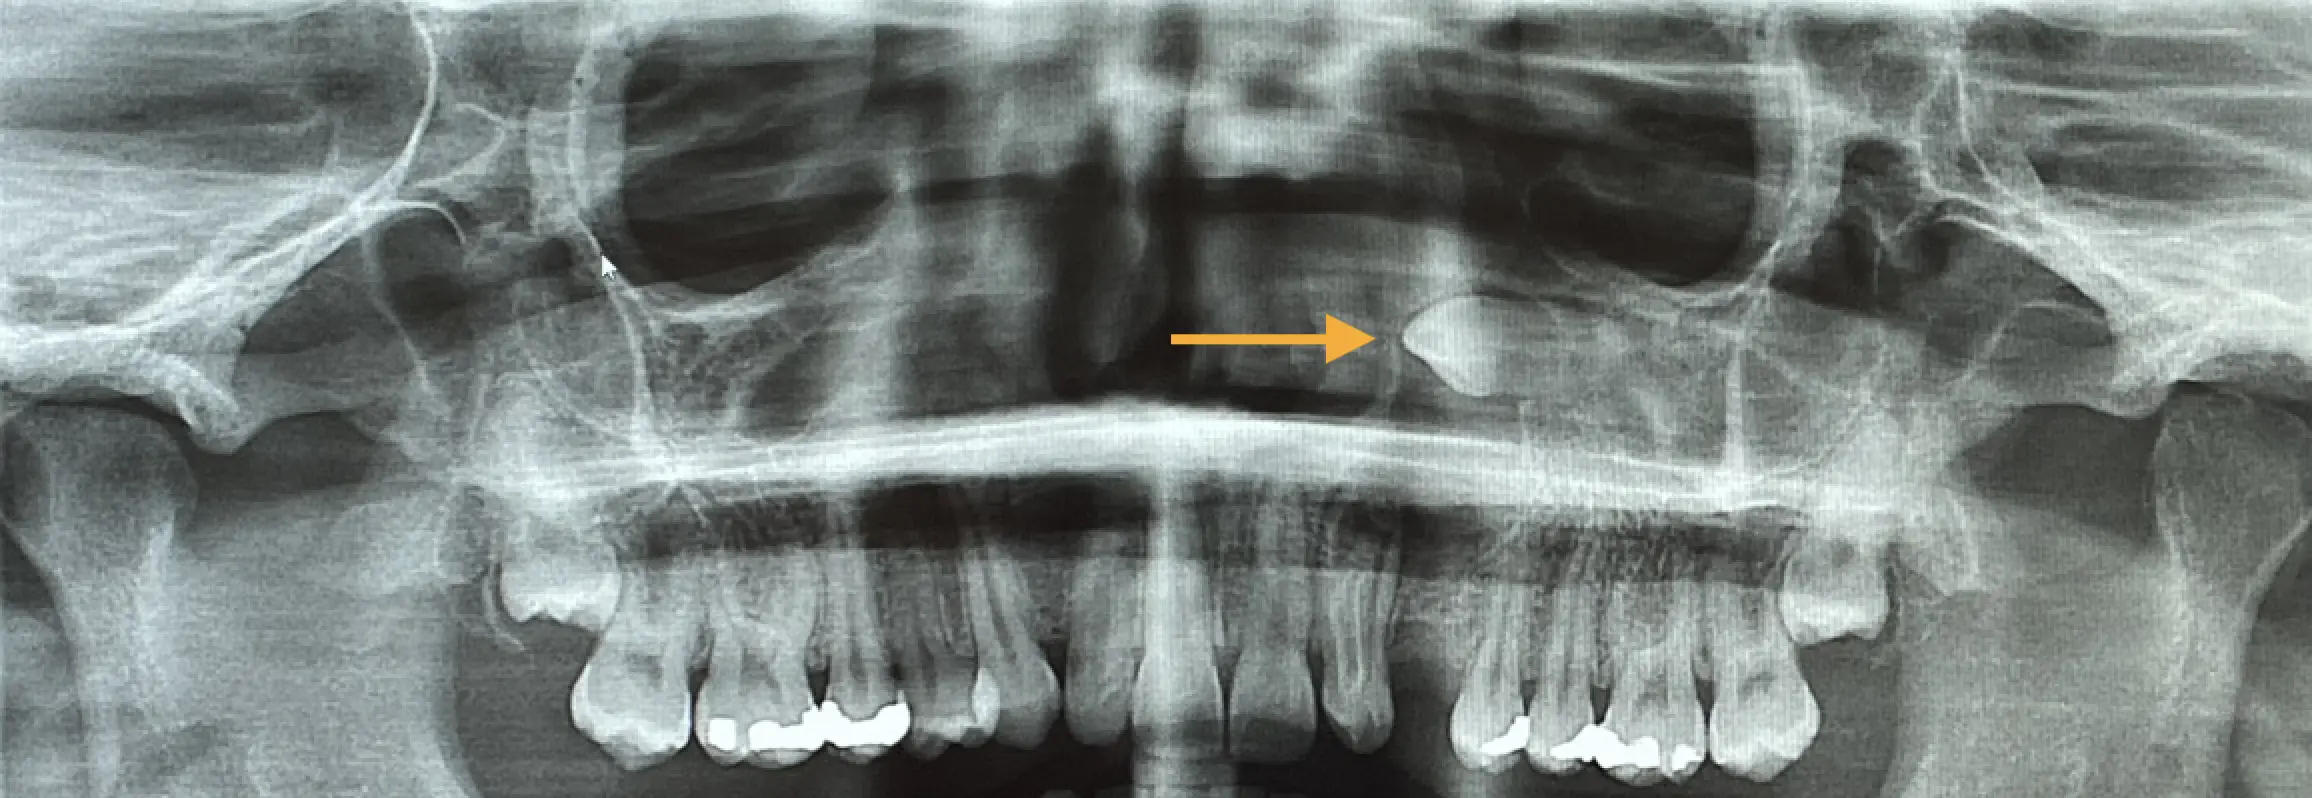

Exposure and traction of impacted teeth are surgical procedures performed to help an impacted tooth properly erupt through the gums and into its normal position in the dental arch. Before the procedure, the surgeon performs a thorough evaluation of the situation using simple or 3D dental x-rays to determine the exact position of the impacted tooth, its orientation, and its relationship to adjacent teeth and surrounding structures. Based on the evaluation, a treatment plan is developed to expose the impacted tooth and allow it to erupt through the gums. After exposing the impacted tooth, an orthodontic appliance may be attached to the tooth to help guide its eruption through the gums and into its proper position in the dental arch. Subsequently, light and controlled force is applied to the impacted tooth to gradually guide it through the gums and into its final position in the dental arch.